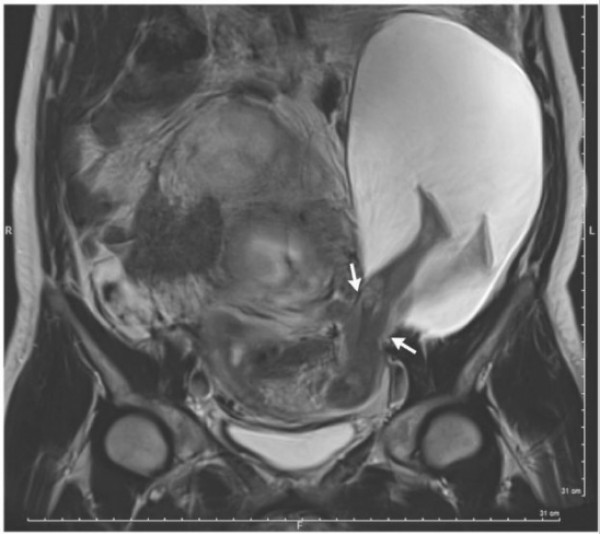

وبعد فحص جنين المرأة باستخدام تصوير الرنين المغناطيسي، أكد بويه أن "رجلي الجنين لم تتسبب في الفتق". وأضاف: "من المحتمل أن تكون الندوب نتيجة الولادات القيصرية الخمسة التي أجرتها المرأة سابقاً، أدت إلى التمزق".

وأوضح: "بقيت أجزاء من الرحم متيبّسة، بدلاً من أن تتضخّم في الحجم خلال الحمل الأخير، ما أدى إلى تمزّق جدار الرحم بطول بوصة، إذ لم يعد قادراً على التمدد".

وغالباً ما يتسبب التمزق في جدار الرحم إلى نزيف داخلي، إلا أن المريضة لم تظهر عليها أي أعراض، وذلك لأن رجلي الجنين سدّتا التمزق، ما منع فقدان الدمّ.